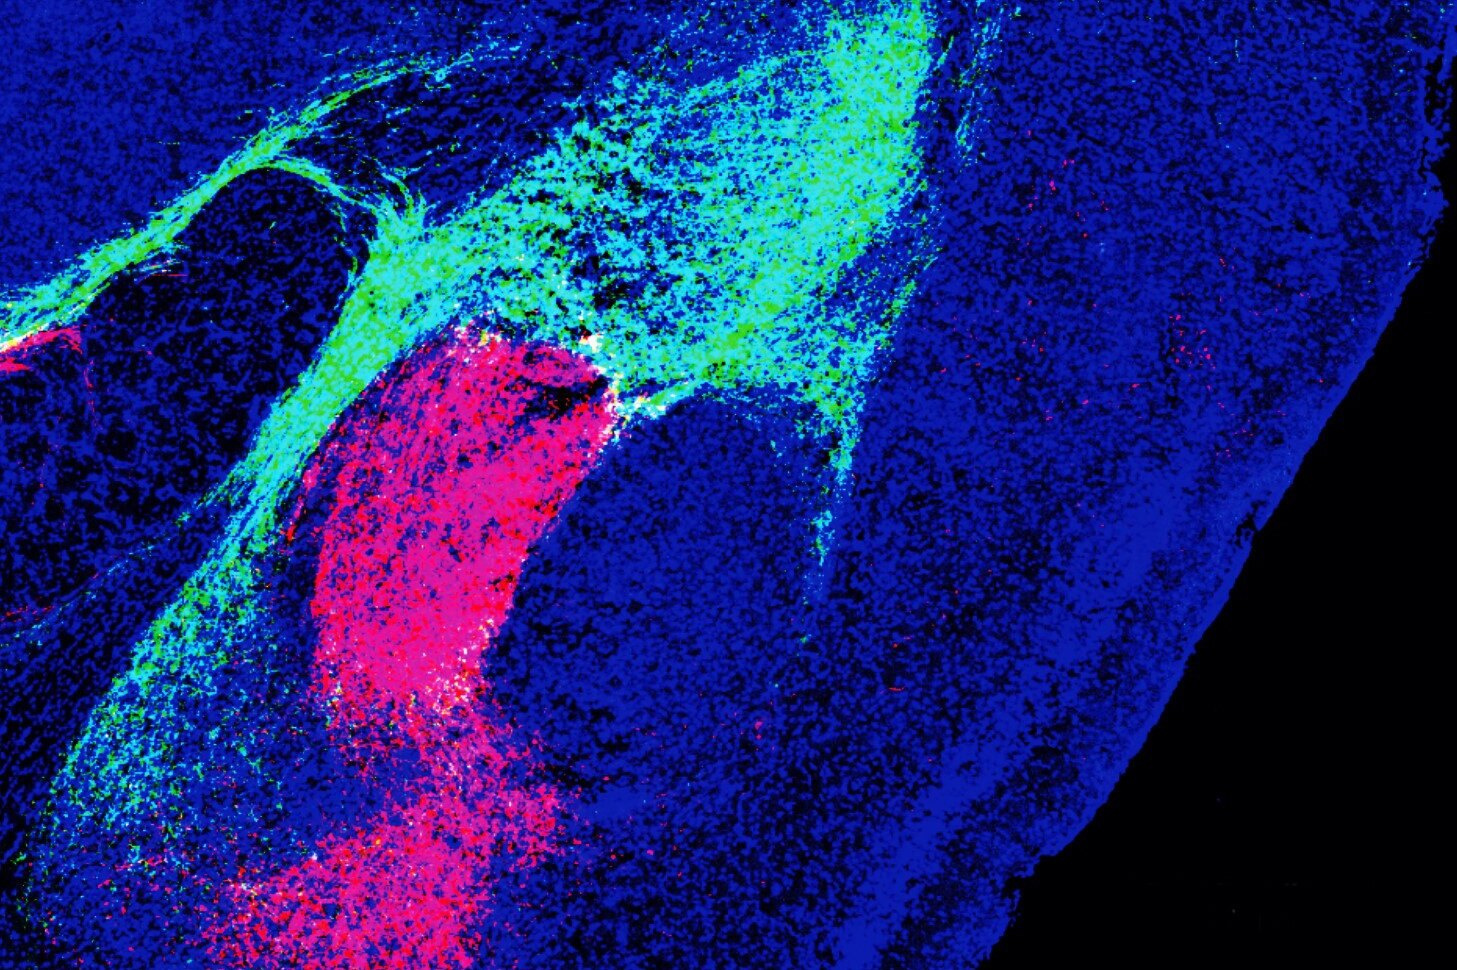

Ученые из Института Солка обнаружили молекулярный путь, который объединяет угрожающие образы, звуки и запахи в одно сообщение: «Бояться!». Молекула под названием CGRP позволяет нейронам двух разных областей мозга объединять угрожающие сенсорные сигналы в один, помечать его как негативный и передавать в миндалевидное тело, которое "включает" чувство страха. Это важный шаг в лечении многих нервных расстройств, в том числе аутизма.

Исследование, опубликованное учеными из Института Солка, может привести к новым методам лечения расстройств, связанных со страхом, таких как посттравматическое стрессовое расстройство (ПТСР) или расстройства гиперчувствительности, такие как аутизм, мигрень и фибромиалгия (хроническая мышечная боль).

Предыдущие исследования показали, что различные нейронные пути независимо передают звуковые, визуальные и сенсорные сигналы угрозы в несколько областей мозга. Единственный суммарный сигнал, объединяющий все эти частные сообщения, был бы полезен для выживания, поскольку реакция на него является быстрой и однозначной. Но до сих пор понять, как формируется такой сигнал,